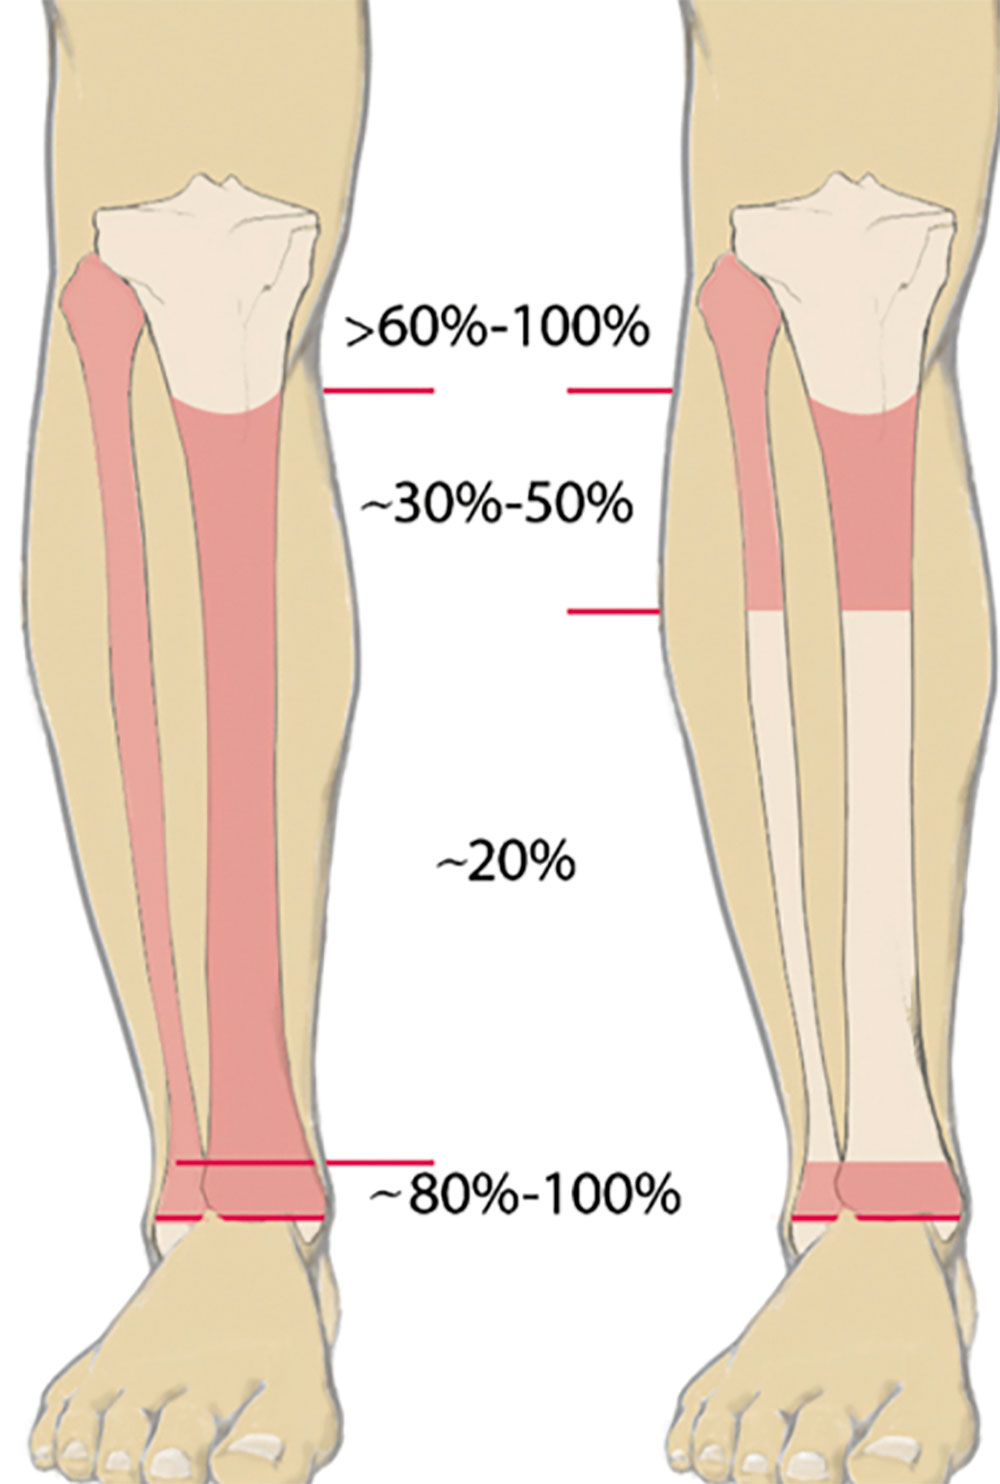

Um eine passgenaue und funktionsfähige Versorgung zu ermöglichen, muss dem Techniker bewusst sein, welche Bereiche des Stumpfes er zur Be- und Entlastung einbeziehen kann. Knöcherne Prominenzen (Abb. 1), eventuelle Neurome und andere empfindliche Areale müssen entsprechend eingebettet werden. Die Bereiche, in denen mehr Weichteile angesiedelt sind, sollten hingegen zur Belastung genutzt werden (Abb. 2). Bei genauerer Betrachtung wird deutlich, dass die Körperlast bei einer Amputation ohnehin nur auf wenige Areale übertragen werden kann. Wenn dann noch ein Amputationsniveau gegeben ist, das relativ weit proximal liegt, verkleinert sich die nutzbare Fläche umso mehr. Aber nicht nur die mangelnde Fläche zur Aufnahme der Körperlast erschwert die Nutzung der Prothese – mit abnehmender Stumpflänge schwindet auch der wirksame Hebelarm zur Steuerung der Prothese. Der Vorteil einer Amputation im proximalen Drittel hingegen zeigt sich bei der erhöhten Stumpfendbelastbarkeit, die bei Amputationen im spongiösen Bereich bei bis zu 100 % liegen kann (Abb. 3). Die roten Bereiche in Abbildung 3 zeigen die geeigneten Amputationsebenen am Unterschenkel – links bei ungestörter, rechts bei gestörter Durchblutung 1.